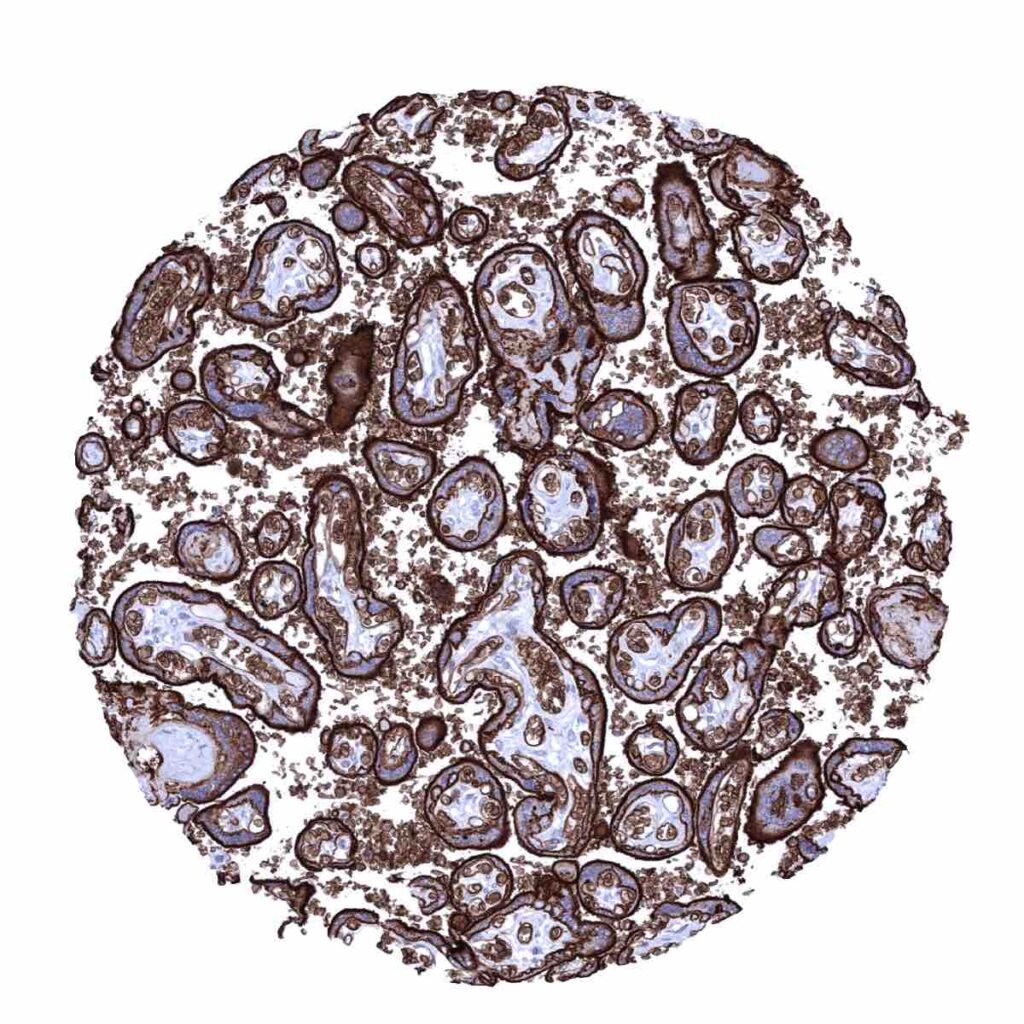

GLUT1 (MSVA401R) MS Validated Antibodies Protein Atlas Glut1 The atlas for all human proteins in cells and tissues using various omics: Here we report the crystal structure of human glut1 at 3.2 å resolution. Glut1 is an integral membrane hydrophobic protein that comprises of 492 amino acids with a molecular weight of 54 kda. Protein Atlas Glut1.

GLUT1 (MSVA401R) MS Validated Antibodies Protein Atlas Glut1 Here we report the crystal structure of human glut1 at 3.2 å resolution. The atlas for all human proteins in cells and tissues using various omics: Glut1 is an integral membrane hydrophobic protein that comprises of 492 amino acids with a molecular weight of 54 kda. Protein Atlas Glut1.

GLUT1 (MSVA401R) MS Validated Antibodies Protein Atlas Glut1 Here we report the crystal structure of human glut1 at 3.2 å resolution. Glut1 is an integral membrane hydrophobic protein that comprises of 492 amino acids with a molecular weight of 54 kda. The atlas for all human proteins in cells and tissues using various omics: Protein Atlas Glut1.